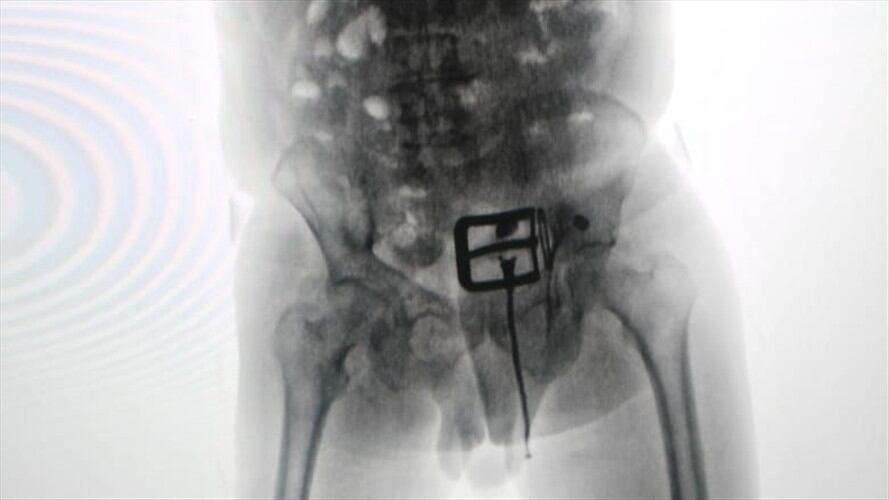

En medio de los controles de la Policía Antinarcóticos en el aeropuerto El Dorado, un uniformado detectó que un adulto mayor realizaba movimientos extraños e ingresaba constantemente al baño, por lo que fue conducido a la sala de rayos X, donde le encontraron 87 cápsulas de cocaína.

El hombre tenía en su interior más de un kilo de la droga, la cual fue extraída en un centro asistencial.